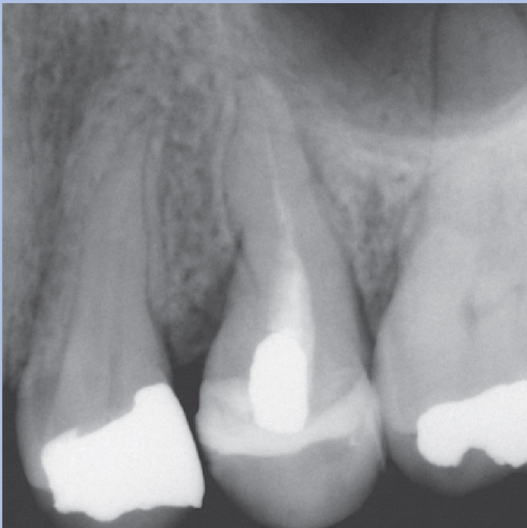

After

After Root Canal treatment